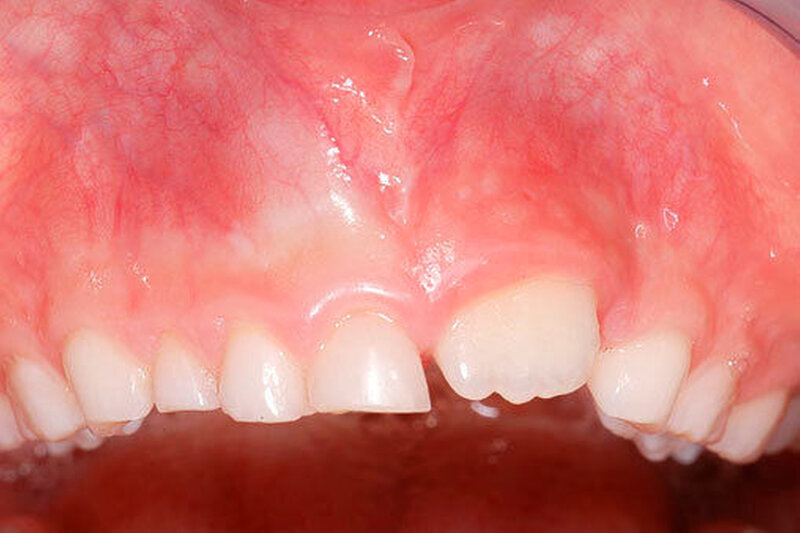

Die Prävalenz überzähliger Zähne wird im Bereich von 0,07 Prozent bis 0,6 Prozent für das Milchgebiss [Luten, 1967; Ravn, 1971; Järvinen Lehtinen, 1981; Magnússon 1984; Skrinjari Barac-Furtinovi, 1991; Yonezu et al., 1997; Chen et al., 2010] und von 0,3 Prozent bis 3,2 Prozent für die bleibenden Zähne [Luten, 1967; Bäckman Wahlin, 2001; Salcido-García et al., 2004; Leco Berrocal et al., 2007; Gündüz et al., 2008; Yagüe-García et al., 2009; Schmuckli et al., 2010; Fardi et al., 2011] angegeben. Die Mehrheit der überzähligen Zähne im Milchgebiss sind seitliche Schneidezähne im Oberkiefer, die meist mit einer normalen Morphologie und Lage durchbrechen (Abbildungen 1 bis 3) [Luten, 1967; Humerfeld et al., 1985; Garvey et al., 1999; Ferrés-Padró et al., 2009]. Der oft ungestörte Durchbruch und das Ausbleiben von Symptomen führen dazu, dass überzählige Zähne in der Milchdentition oft gar nicht diagnostiziert werden, und dies wird auch als Erklärung für die unterschiedlichen Prävalenzen überzähliger Zähne im Milch- und bleibendem Gebiss angeführt [Wang Fan, 2011]. Überzählige Zähne sind häufiger bei Männern als bei Frauen, wobei über ein Verhältnis von 1,18:1 bis 4,5:1 berichtet wird [Rajab Hamdan, 2002; Fernández Montenegro et al., 2006; Gündüz et al., 2008; Wang Fan, 2011]. In der Schweiz publizierten von Arx (1990) und Schmuckli und Mitarbeiter (2010) Geschlechterverhältnisse von 2,6:1, beziehungsweise 2,75:1. In einer aktuellen Arbeit von Mossaz und Mitarbeiter (2014) von Patienten aus dem Raum Bern lag dieses Verhältnis etwas ausgeglichener bei 1,61 zu 1.

Die überzähligen Zähne mit identischer Zahnform finden sich normalerweise beim oberen seitlichen Schneidezahn. Zusätzliche Prämolaren und Molaren können aber auch auftreten. Die Mehrheit der überzähligen Zähne im Milchgebiss sind vom identischen Zahnform-Typ und bleiben nur selten impaktiert oder retiniert.